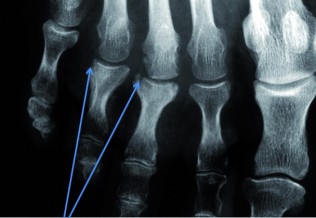

Arthroses digitales érosives : un effet structural potentiel du méthotrexate